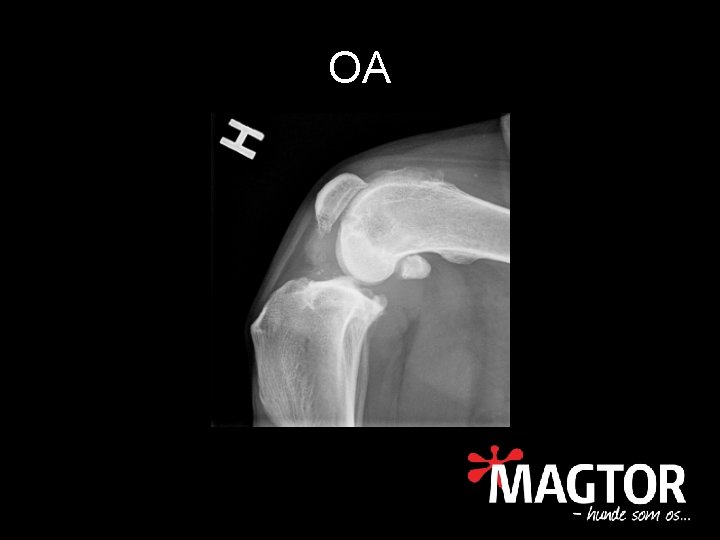

Slidgigt • • • Osteoarthrose (OA) Nedbrydning af brusk Knoglenydannelse Kronisk inflammation Nedsat bevægelighed Smerte af flere årsager

OA